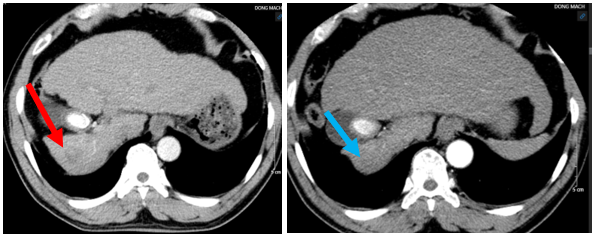

- Hình ảnh chụp cộng hưởng từ ổ bụng, cắt lớp vi tính ngực (tháng 3/2024):

Hình 5: Hình ảnh chụp cộng hưởng từ ổ bụng (bên trái) và hình ảnh chụp cắt lớp vi tính ngực (bên phải)  (Tháng 3/2024): Hình ảnh u gan đa ổ ở hạ phân thùy III, khối lớn nhất có kích thước 45x58mm, không rõ tính chất HCC (mũi tên đỏ). Hình ảnh nốt đặc nhỏ thùy dưới phổi phải kích thước 6 mm (mũi tên xanh).